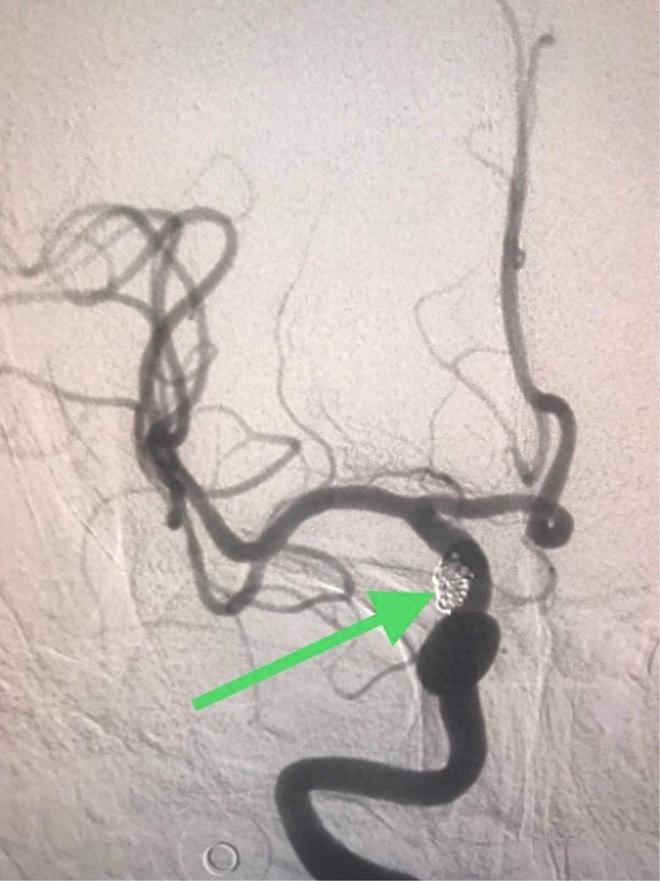

狭窄>70%:重度狭窄,即使没有症状,脱落和闭塞的风险也非常高,可能需要介入治疗(支架或内膜剥脱)。